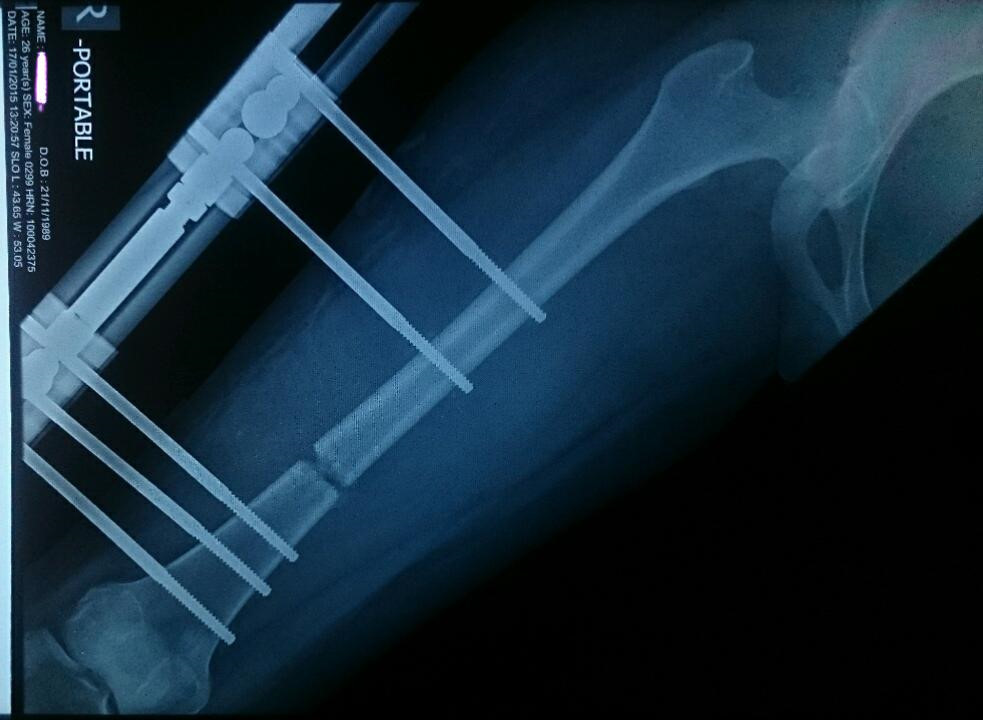

Trong đó, chân hoặc tay bệnh nhân được tăng chiều dài bằng cách cưỡng ép xương phát triển. cuộc phẫu thuật đầu tiên sẽ làm xương gãy và gắn vòng thép không gỉ vào xương bằng các đinh ghim. Khi xương gãy bắt đầu liền lại, bác sĩ sẽ điều chỉnh để khoảng cách giữa các vòng rộng ra (4 ngày một lần) để ép xương phát triển lấp lại khoảng trống, thường là một mm mỗi ngày.

Sau khi quá trình kéo dài hoàn tất, khung thép được giữ nguyên trong giai đoạn củng cố. Bệnh nhân có thể sử dụng nạng để đi lại và trải qua một cuộc phẫu thuật thứ hai để tháo khung. Ngoài ra, họ còn có thể phải phẫu thuật để kéo dài dây chằng Achilles để phù hợp với phần xương đã thay đổi. Quy trình đấy đau đớn này được sử dụng cho mục đích trị liệu, nhưng không ít người khỏe mạnh sẵn sàng trải qua những cơn đau để có được chiều cao như ý.